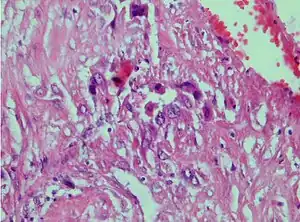

| Photomicrograph showing proliferating intermediate trophoblast with scarce cytotophoblastic and syncytiotrophoblastic elements | |

A placental site trophoblastic tumor is a monophasic neoplasm of the implantation site intermediate trophoblast, and usually a benign lesion, which comprises less than 2% of all gestational trophoblastic proliferations. Preceding conditions include molar pregnancy (5%). Compared to choriocarcinoma or invasive mole, hemorrhage is less conspicuous and serum β-HCG level is low, making early diagnosis difficult.

Immunohistochemistry: Often stains with hPL, keratin, Mel-CAM, EGFR.